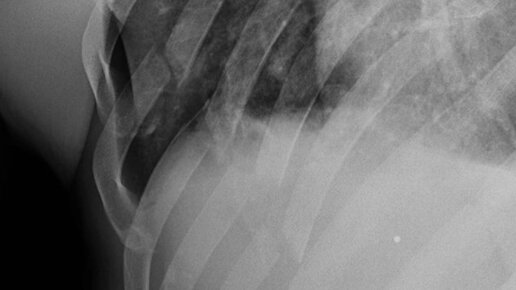

Перелом 5 ребер, повреждение легкого и пневмоторакс